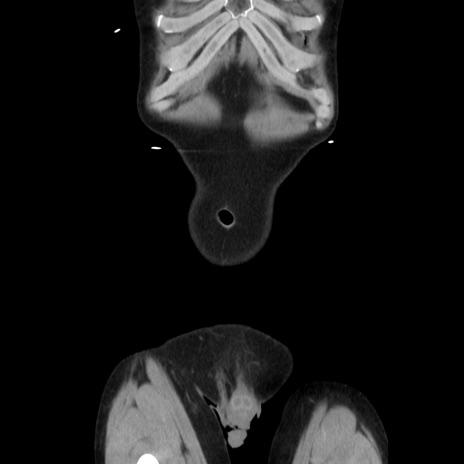

症例37(冠状断像)

【症例】40歳代 男性

【主訴】腹痛

【現病歴】4時間ほど前に電車に乗車中に臍部上より腹痛出現。徐々に増悪し起立困難となり、救急外来受診。生ものは数日食べていない。今朝お雑煮を食べた。

【身体所見】BT 36.8℃、BP 117/84mmHg、HR 91/min、SpO2 97%、苦悶様、腹部:臍上部広範囲圧痛あり、反跳痛±

【データ】WBC 8100、CRP 0.03